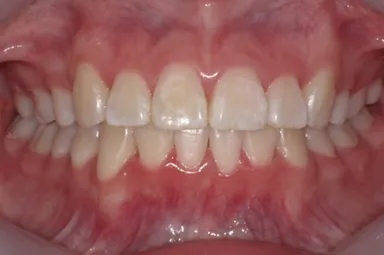

13歳8か月の女子(初診時:写真a)

主訴は左上に八重歯がある。右側Angle ClassII 左側Angle Class I、FMA 36.6°、A.L.D.(凸凹の量/上顎 -10.0mm、下顎 -4.0mm)

前歯部のトルクコントロール、上下顎の正中の一致、犬歯関係、大臼歯関係が良好になり、咬合関係が改善。(写真c)

c:7か月後